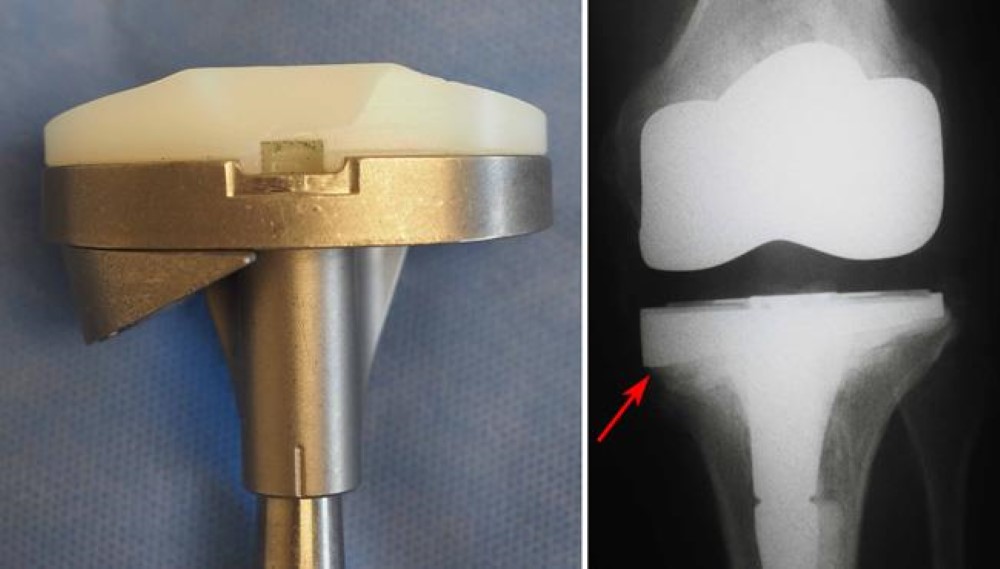

The main reason for replacing any arthritic joint with an artificial joint is to stop the bones from rubbing against each other, which is the cause of knee joint pain. The main aim of this Primary Total Knee Replacement Surgery is to help people return to many of their activities with less everyday pain, knee joint pain with greater freedom of movement.

In this implant the femoral component is made of stainless steel and the tibial tray and the insert are together made of polyethylene. The advantage it has is that more poly is available and hence it lasts longer, also cost-wise it is cheaper than the other implants.

Rotating Platform Knee

The Rotating Platform Knee is based on a revolutionary design technology, the Mobile-bearing Knee. When patients bend their Knees, the surfaces of their joints roll and glide against each other, allowing their knees to rotate as they bend.

Unlike traditional, Fixed-bearing Knee implants, Rotating Platform Knee Implants are designed to mimic this natural movement. This rotation reduces the stress and wear on the implant. Women may be especially interested in this technology, since their Knees rotate more than those of a man during normal movement.

The disadvantage of this Knee is that if there is a gross deformity or imbalance in the ligament, then there are chances of dislocation of the Knee after using rotating platform Knees.